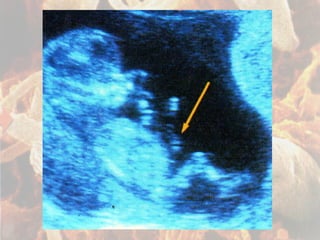

Fecundação Nidação Oócito II